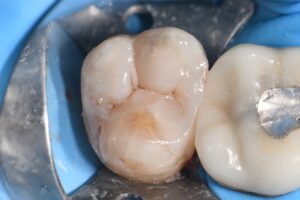

March 10, 2026 (Afternoon tea pics 2341.3: Kerr Simplishade | Rhondium DME | Garrison Dental Solutions – North America) Getting d o w n with DME. #RhondiumDME #KerrSimplishade #GarrisonCompositight Previous Post